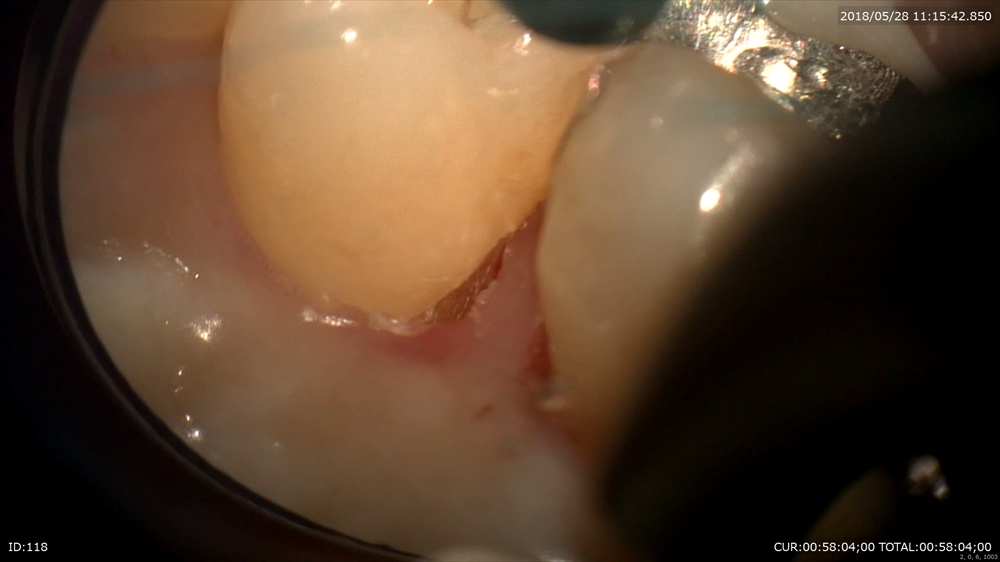

その解説した本日の朝のケースはこちら。

メンテナンス中にポケットが深くなった。

どうでしょう。歯ブラシの良さもあいまって歯周病に罹患しているとは思えないくらい綺麗。

でも検査結果は嘘をつかない。ポケット6mmの現実

16倍拡大。ほら。いらした衛生士さんもびっくりしていました。